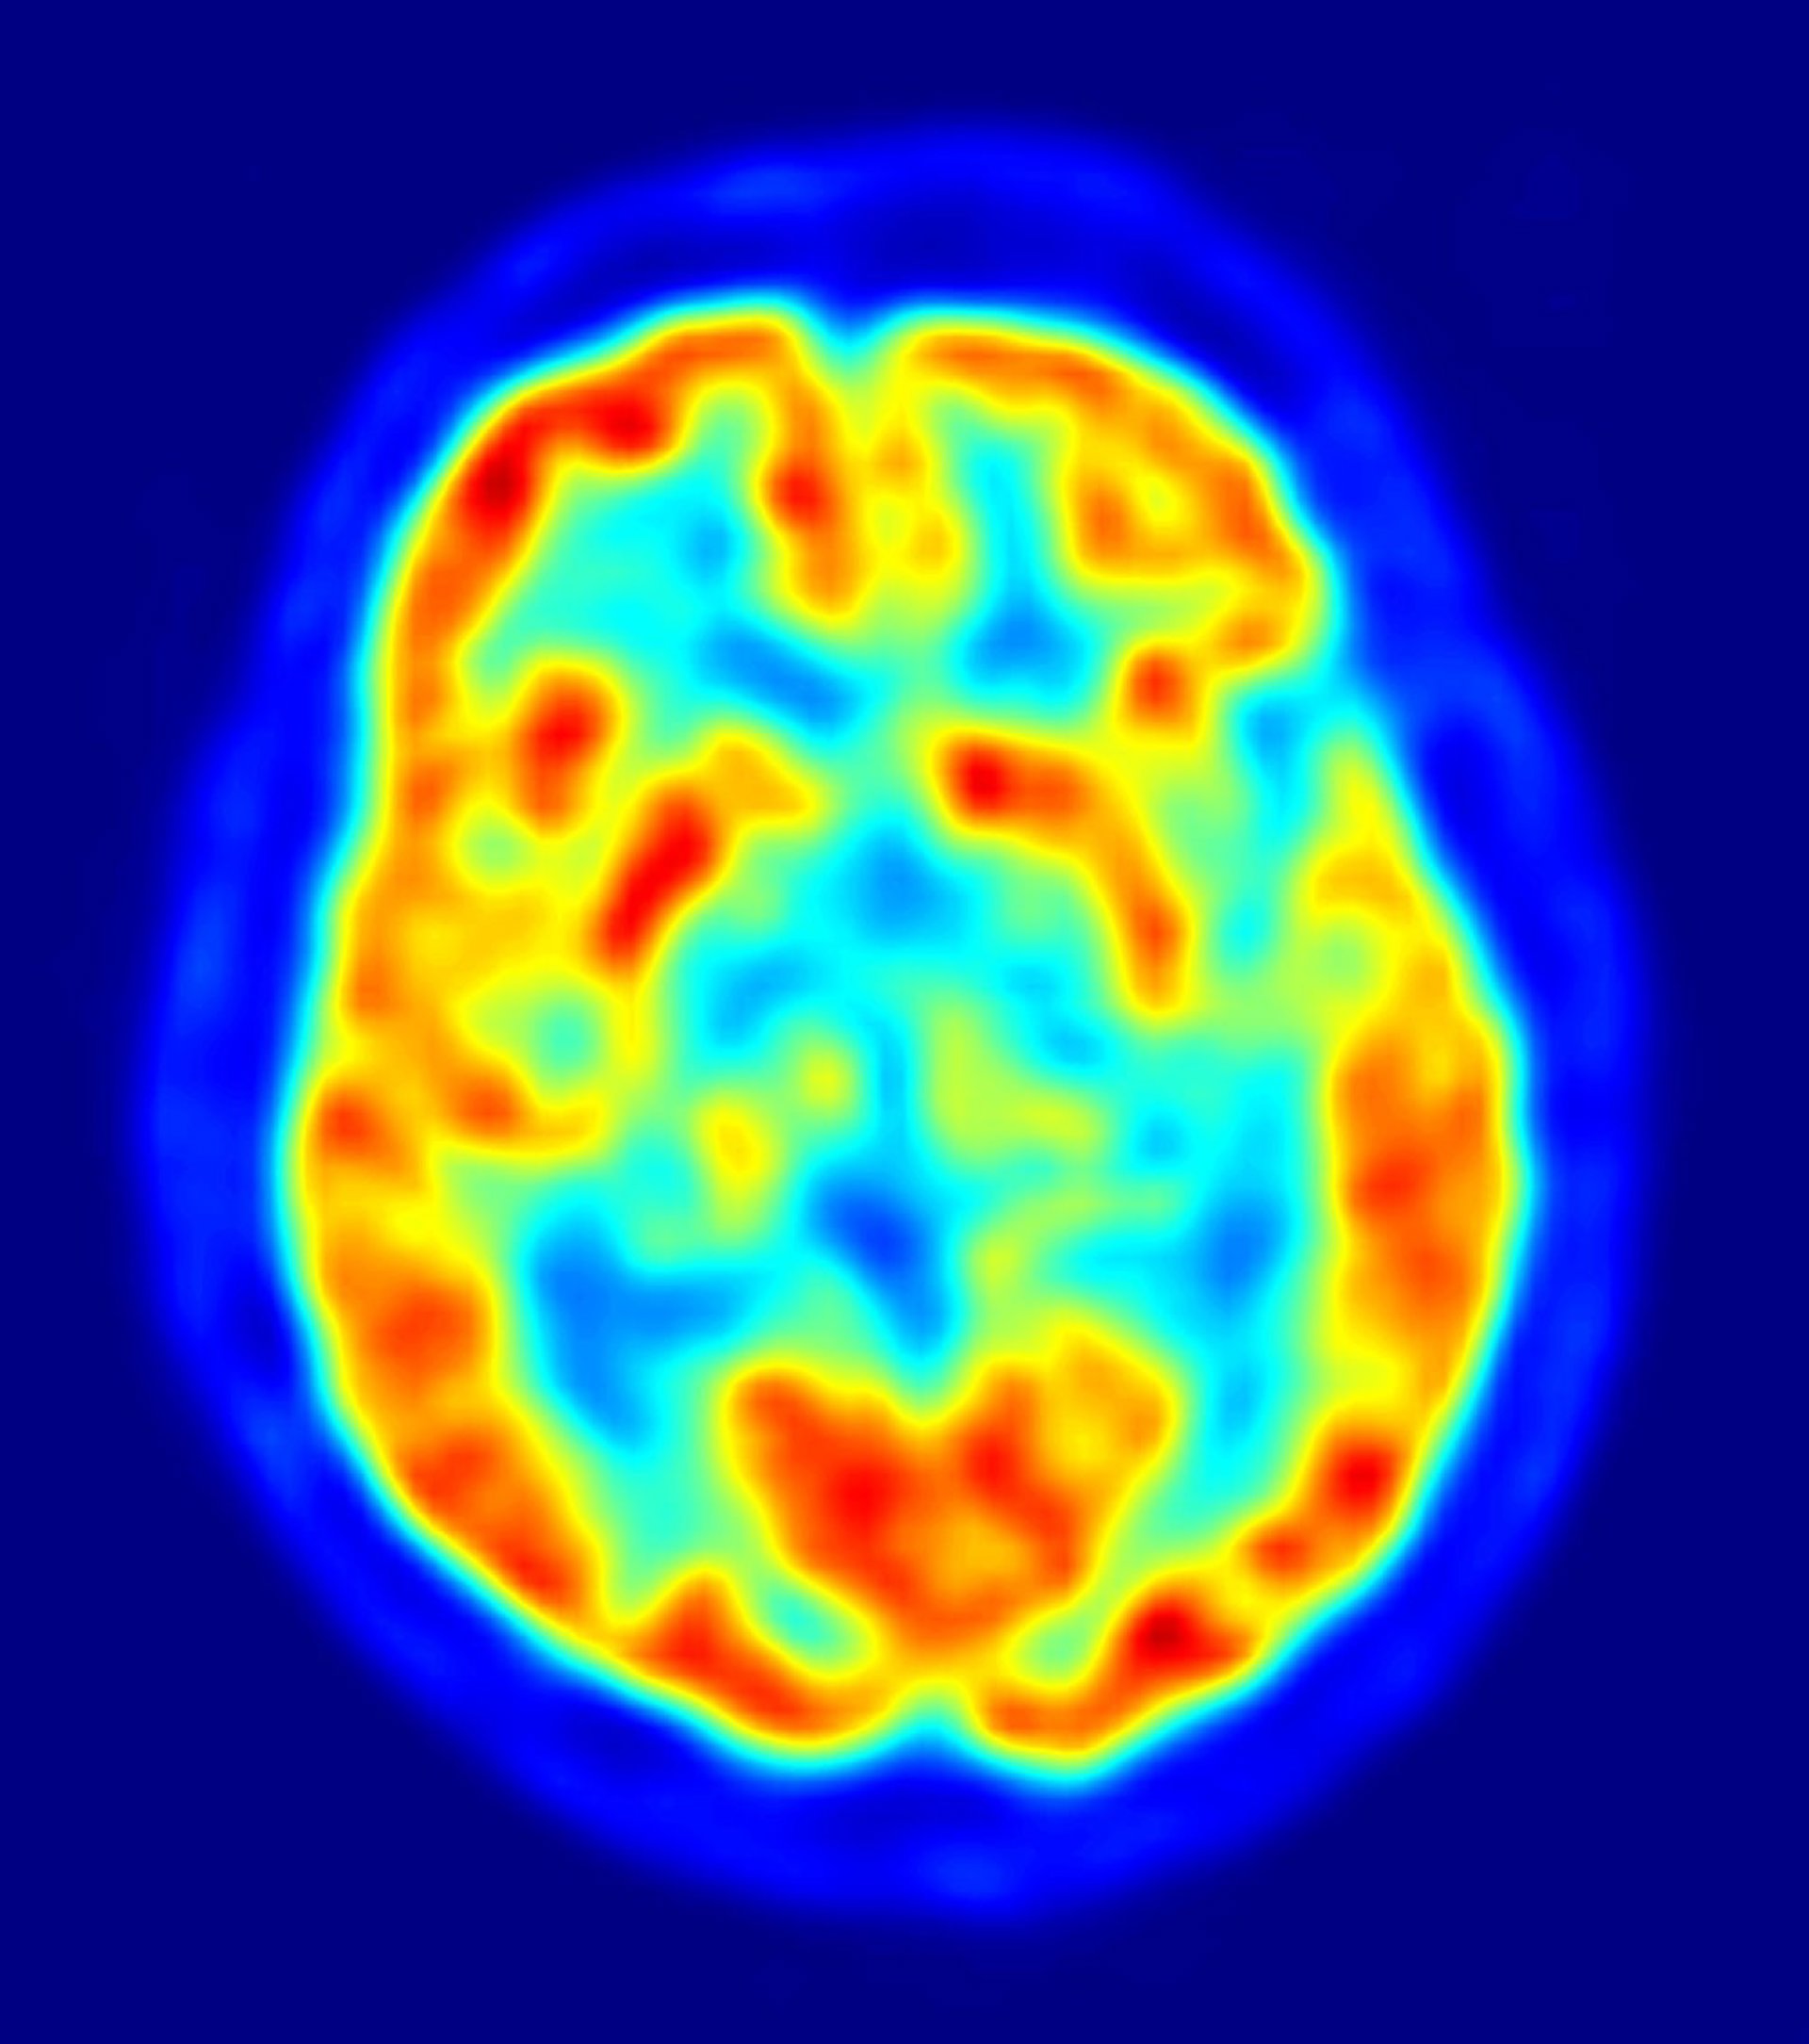

La capacidad de percibir la realidad en tres dimensiones se desarrolla en la corteza cerebral temporal inferior, donde la actividad neuronal en esta región crea una representación del objeto donde se capta además su profundidad, según un estudio llevado a cabo por expertos de la Universidad de Leuven en Bélgica.

El hallazgo, publicado en la revista 'Neuron', ha sido realizado en primates. "La corteza temporal inferior es responsable del reconocimiento de objetos. Tanto en monos como en humanos, cuando existe una lesión en ella se puede padecer agnosia, la incapacidad para reconocer objetos o estímulos ya aprendidos", aclara Janssen.

Los investigadores estimularon grupos de neuronas en la corteza temporal inferior con pequeñas descargas mientras trataban de decidir si una superficie era cóncava o convexa. "Al observar un balón de fútbol, por ejemplo, inmediatamente sabemos que tiene profundidad, que no es plano sino convexo y con estructura tridimensional", explica.